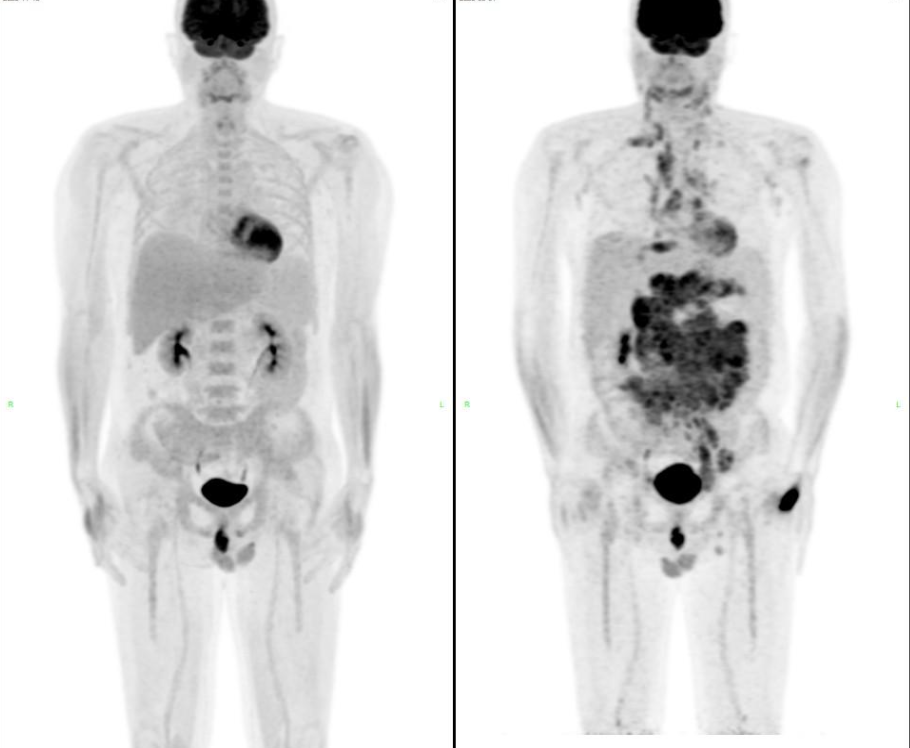

• 2025-11-18 PET-CT评估示全身代谢异常淋巴结基本消失,胸腹水消退,疗效达CR。

2025-11-18(左)与2025-08-01(右) PET-CT